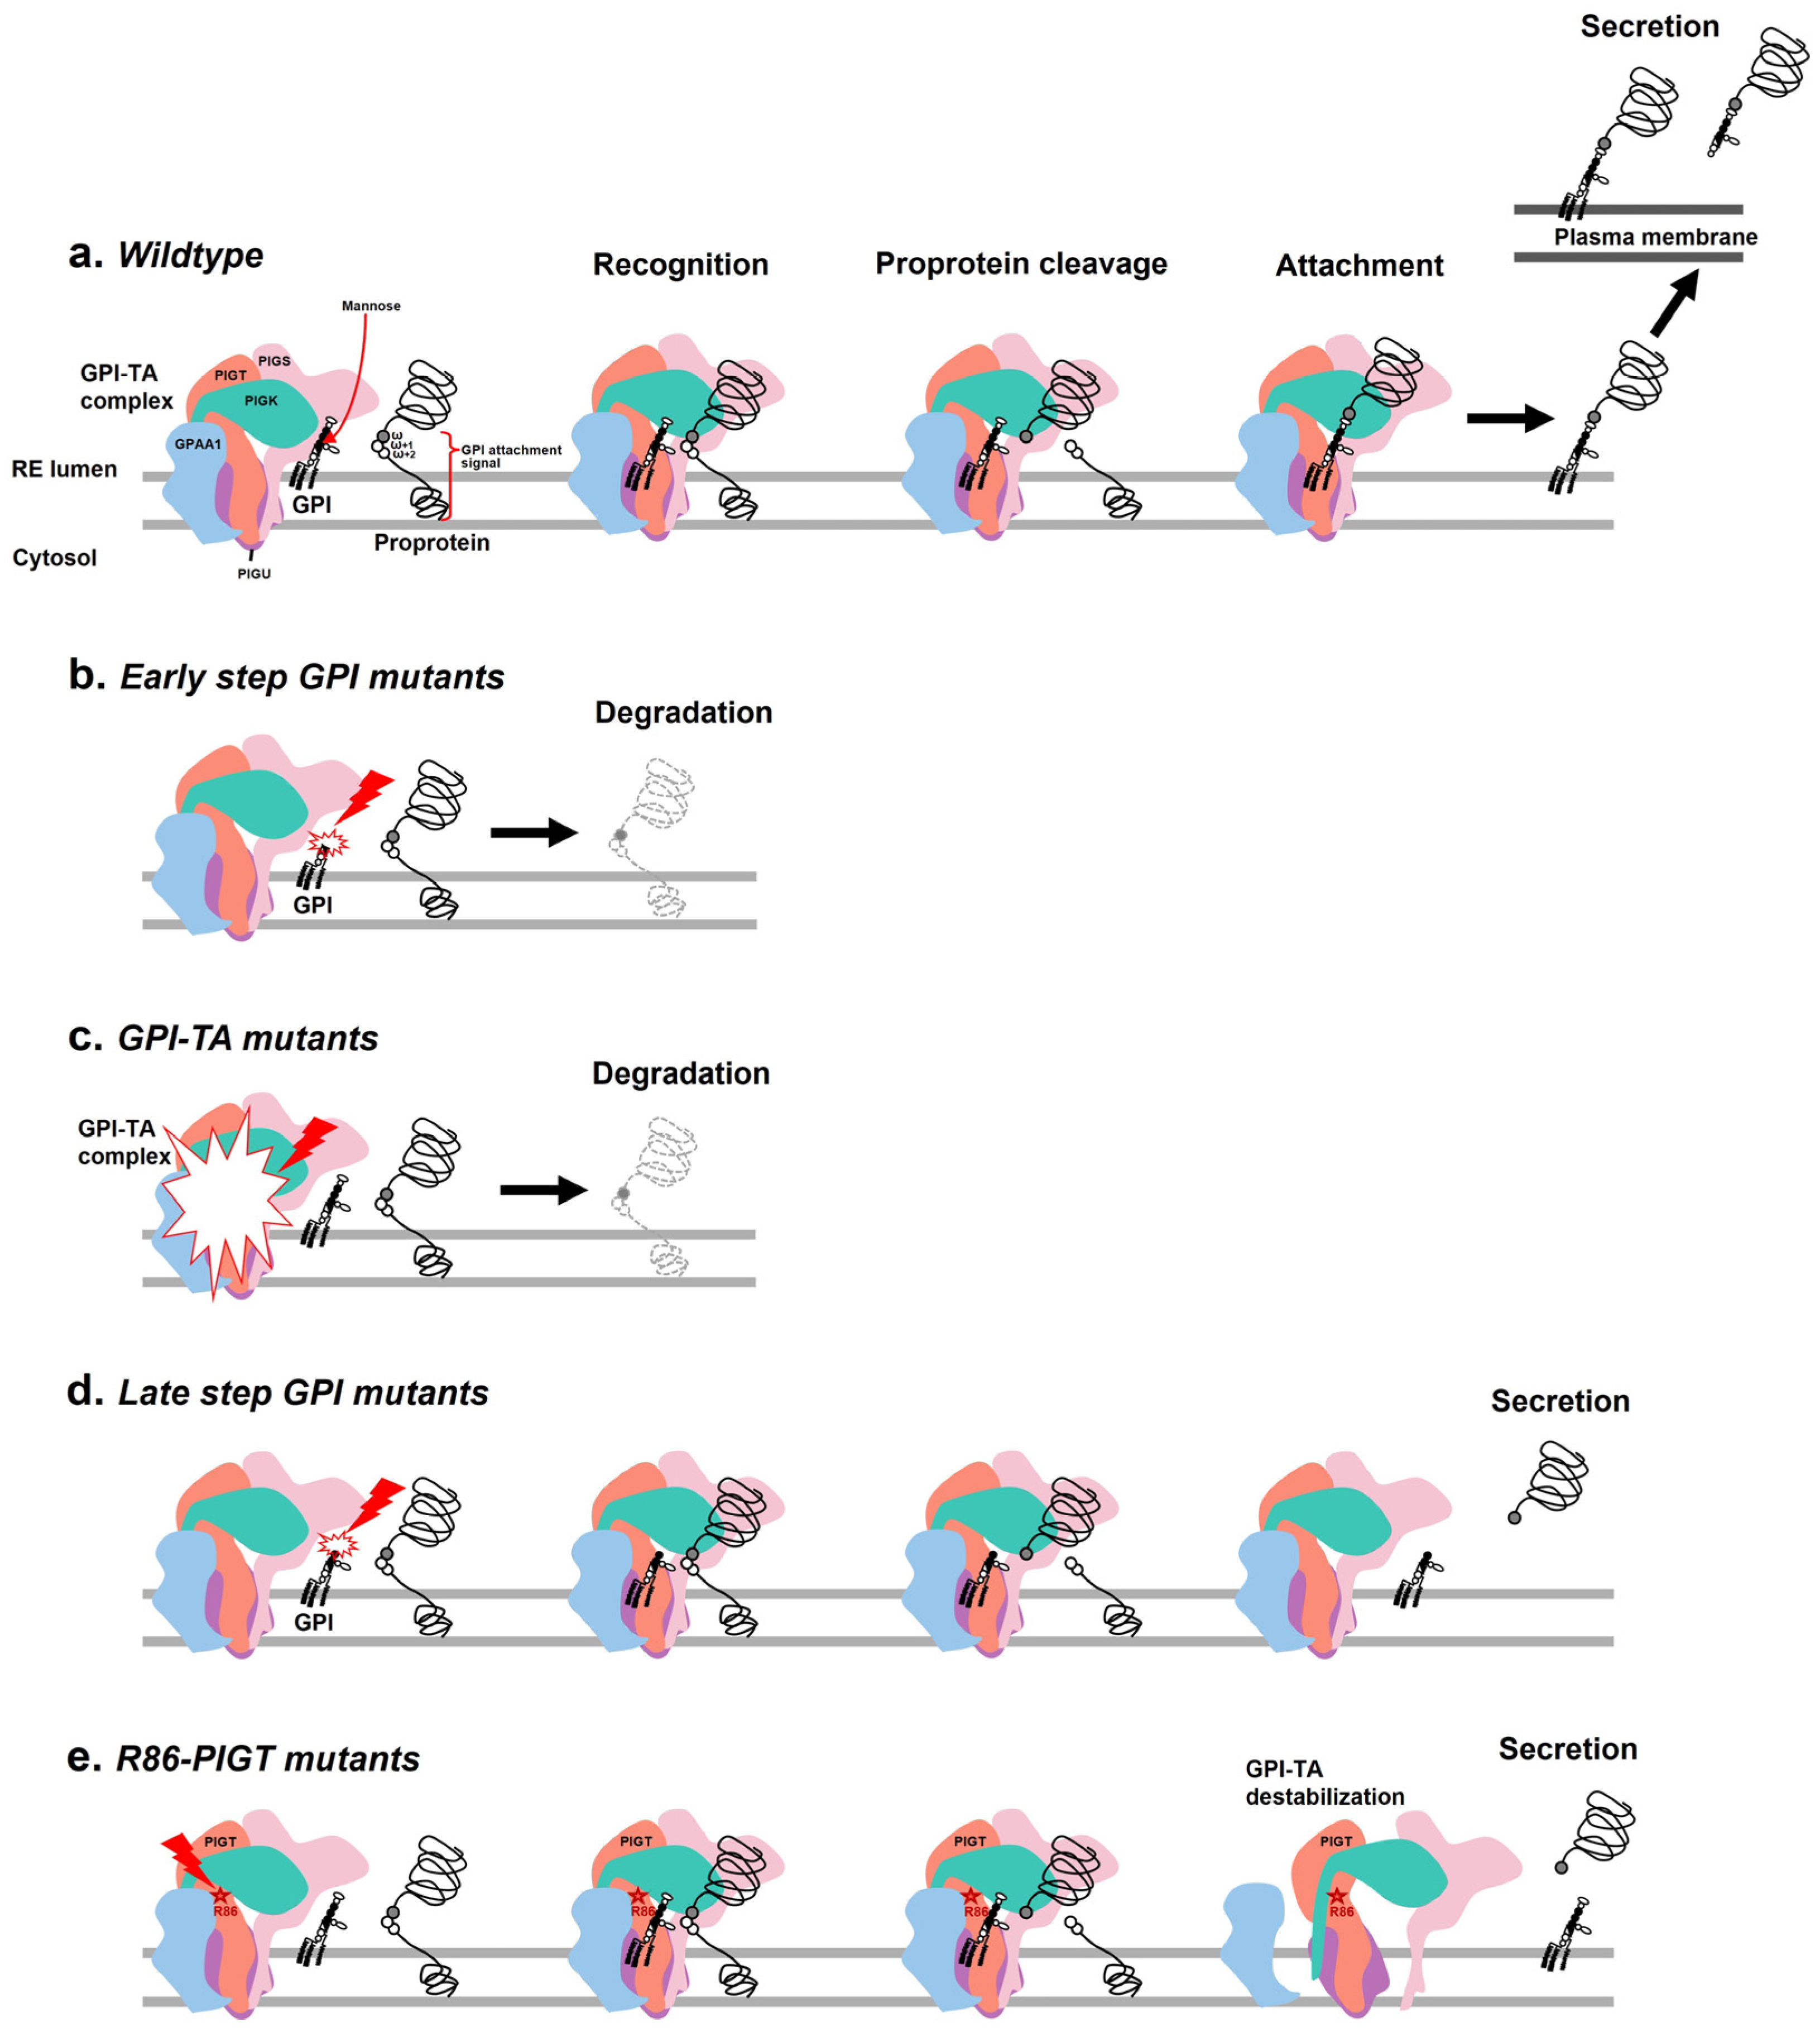

2.3. Effects of the c.257A>G on PIGT Function Demonstrated by GPI-AP Expression Analysis

3. Discussion